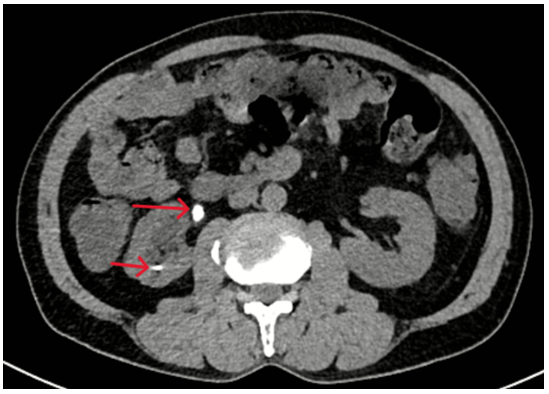

- Chụp CT bụng: Hình ảnh giãn đài bể thận và niệu quản phải do sỏi niệu quản đoạn 1/3 trên. Sỏi đài dưới thận phải.

Hình 2: Thận phải: Hình dạng và kích thước bình thường, nhu mô có nang 32mm. Đài bể thận giãn đường kính trước sau 15mm, đài dưới có sỏi kích thước 5mm. Niệu quản đoạn 1/3 trên giãn đường kính 9mm, có sỏi kích thước 7x13mm.